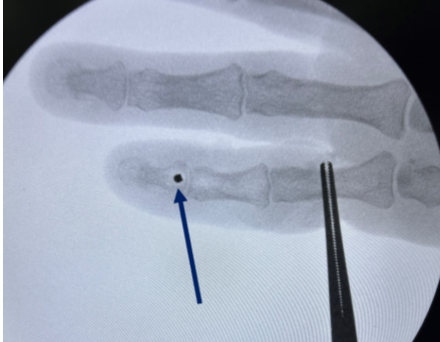

A 59-year-old right-handed patient presented with complaints of limited movement, pain, and swelling in her left fifth finger following blunt trauma to her hand. The injury occurred during a fall at home a month ago, and she reported persistent loss of distal flexion and mild swelling. Clinical examination revealed a complete loss of active flexion of the distal interphalangeal (DIP) joint of the left fifth finger, consistent with FDP avulsion. No advanced imaging, such as ultrasound or magnetic resonance imaging (MRI), was performed, as the diagnosis was clinically evident and surgical exploration was already indicated due to the delayed presentation. A small bone fragment was detected to be avulsed on the radiograph.

Under local anesthesia and without using a tourniquet, a Brunner incision was made distal to the volar aspect of the fifth finger (Fig. 1).

Figure 1: Determination of distal incision line.

Considering that the ruptured tendon due to bone avulsion did not escape to the proximal A4 pulley, only a distal incision was made at first. However, after exploration, it was determined that the A4 pulley was ruptured and the tendon was advancing proximally. Then, a mini-incision was made over the A1 pulley. The ruptured tendon was found at the proximal border of the A1 pulley (Fig. 2). The tendon was identified, mobilized, and delivered distally through the pulley system using a silicone rod to avoid damaging the intact pulleys and to facilitate gliding (Fig. 3). After preparing the FDP insertion site in the distal phalanx, the tendon was fixed using a 2.5 mm mini anchor suture (Fig. 4). Since the tendon tension was appropriate, no lengthening procedure was considered for the tendon (Fig. 5). The A4 pulley was repaired with 4/0 surgical suture. The flexor tendon sheath and skin were meticulously closed.

Figure 2: The flexor tendon could be found at the A1 pulley level.